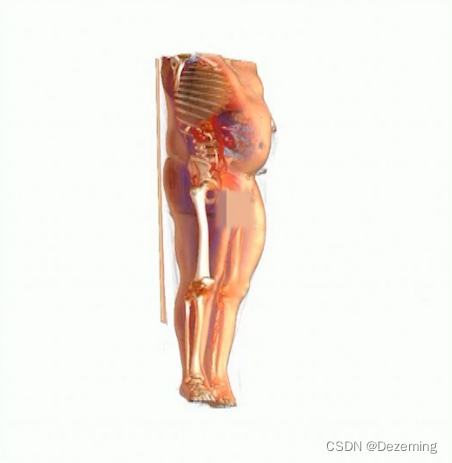

有一个医学影像视频,需要给小弟弟全都打码。这个医学影像视频里的视角还是不断移动的:

而且有些时候小弟弟会消失在视野里。